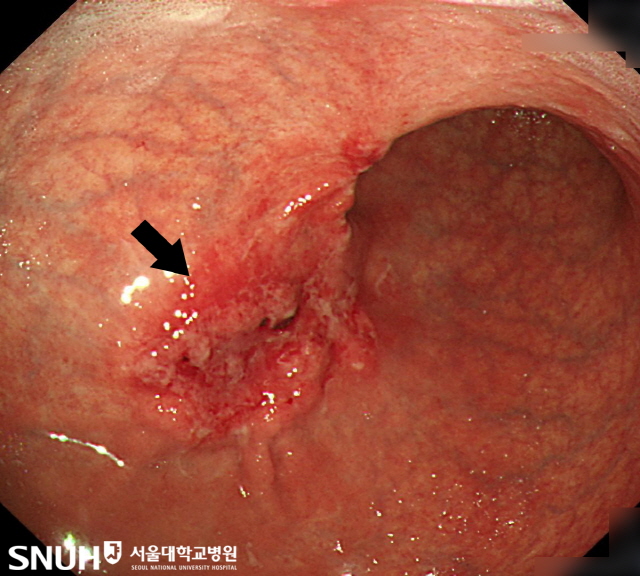

위암은 위안에 악성 종양이 생기는 것을 말하고요. 위암은 세포의 비정상적인 성장과 분열로 인해 발생 해요. 위암은 예사로 위의 상부에 위치하고 있는 점막세포에서 시작되며, 그 다음에는 근육층과 지방층까지 퍼져나갈 수 있어요.

위암은 흔하게 소화기관의 다른 부분에 나타나는 암보다 적게 진단된다 하였습니다. 그렇지만 위암은 초기에는 대다수 증상이 없어서 발견이 곤란한 경우가 대부분입니다 따라서, 위암은 진행되면서 증상이 심해져서야 탐지되는 경우가 많이 들어있다고해요. 그리하여 위암 검진을 꾸준하게 받아서 확인하는게 중요하고요.

위암의 주요 위험 요인에는 흡연, 과한 알코올 소비, 비만, 걸핏하면 반복적인 위산 역류, 과한 소금 섭취, 위암 가족력 등이 있어요. 위암은 조기 발견하고 치료를 받으면 치료 후 경과가 그 이상으로 좋아지고 해서, 지속적인 위암 검진을 통해 조기 발견과 예방에 매진하시는 것이 중요하고요.